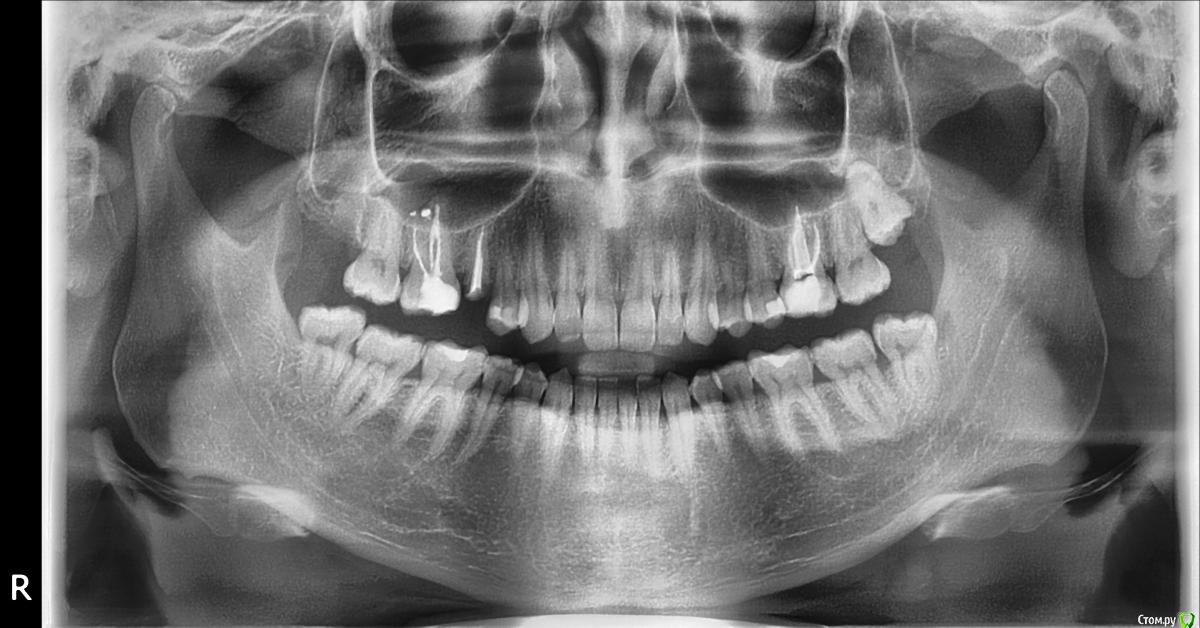

Уважаемые специалисты, что вы можете сказать по поводу верхних 4-5-6 зубов?

Есть ли проблемы в гайморовой пазухе справа и с 5 зубом (вернее его корнем)?

Что за проблема с левой стороне в 6ом зубе. Что может означать трещина в пломбе?

По снимку гайморова пазуха справа чистая.Есть выведение материала но если у вас с той стороны постоянной заложенности носа нет то это  ничего страшного.С корнем все нормально ,но это сугубо по снимку.А так надо во рту визуально оценивать на что он сгодится.Есть карман за 6 зубом.Надо делать коронки и вкладки если корень 5 в хорошем состояние.Слева тоже все нормально но тоже пломбу надо менять на коронку.А "трещина" в пломбе это скорее всего пора или не рентгеноконтрастная прокладка между пломбировкой корневых каналов и постоянной пломбой.Делайте коронки